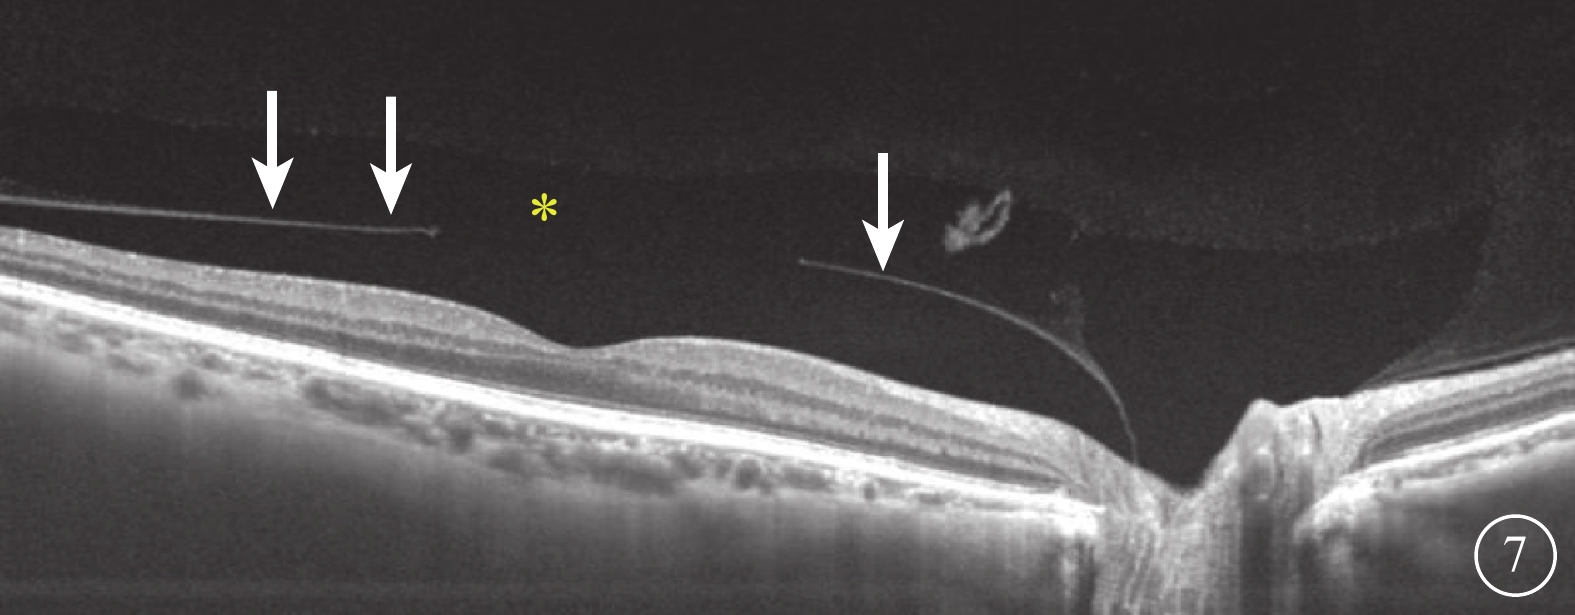

SS-OCT檢查結果顯示,所有受檢眼均在同一掃描層面觀察到PPVP與Martegiani區(圖6),其中PPVP與Martegiani區存在連接通道54只眼(77.0%)。其形態特點與SD-OCT檢查所見相似,但PPVP成像更清晰,與Martegiani區的連接通道更清楚(圖6)。PPVP前存在黃斑上囊7只眼。PPVP伴PVD 4只眼,其中玻璃體后皮質破裂后界不完整(圖7)2只眼。同時行SD-OCT及SS-OCT檢查的24只眼中,SD-OCT、SS-OCT檢查發現PPVP與Martegiani區連接通道分別為18、21只眼;SD-OCT檢查未發現黃斑上囊2只眼,但SS-OCT檢查發現存在。

圖6

受檢眼SS-OCT像。可見PPVP(黃星)與Martegiani區(藍星),以及完整的PPVP和Martegiani區,cloquet管向前延伸(紅色雙箭),玻璃體成像更加平滑、清晰,黃斑上囊結構也更易識別(白色星)

圖6

受檢眼SS-OCT像。可見PPVP(黃星)與Martegiani區(藍星),以及完整的PPVP和Martegiani區,cloquet管向前延伸(紅色雙箭),玻璃體成像更加平滑、清晰,黃斑上囊結構也更易識別(白色星)

SS-OCT檢查結果顯示,所有受檢眼均在同一掃描層面觀察到PPVP與Martegiani區(圖6),其中PPVP與Martegiani區存在連接通道54只眼(77.0%)。其形態特點與SD-OCT檢查所見相似,但PPVP成像更清晰,與Martegiani區的連接通道更清楚(圖6)。PPVP前存在黃斑上囊7只眼。PPVP伴PVD 4只眼,其中玻璃體后皮質破裂后界不完整(圖7)2只眼。同時行SD-OCT及SS-OCT檢查的24只眼中,SD-OCT、SS-OCT檢查發現PPVP與Martegiani區連接通道分別為18、21只眼;SD-OCT檢查未發現黃斑上囊2只眼,但SS-OCT檢查發現存在。

圖6

受檢眼SS-OCT像。可見PPVP(黃星)與Martegiani區(藍星),以及完整的PPVP和Martegiani區,cloquet管向前延伸(紅色雙箭),玻璃體成像更加平滑、清晰,黃斑上囊結構也更易識別(白色星)

圖6

受檢眼SS-OCT像。可見PPVP(黃星)與Martegiani區(藍星),以及完整的PPVP和Martegiani區,cloquet管向前延伸(紅色雙箭),玻璃體成像更加平滑、清晰,黃斑上囊結構也更易識別(白色星)